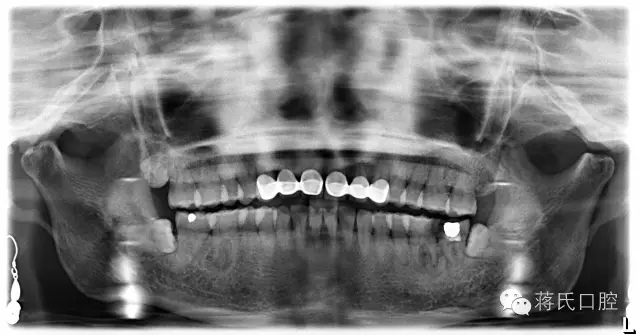

術(shù)前檢查:全景片顯示左下六七殘冠并發(fā)根尖炎癥,骨量豐滿、骨高度良好、但因?yàn)闅埞跁r(shí)間較長,對(duì)合牙伸長,咬合距離低,建議患者正畸治療上牙,但患者拒絕。因?yàn)榛颊呤墙處熉殬I(yè)所以在設(shè)計(jì)方案及治療溝通中詳細(xì)醫(yī)囑,每次治療均經(jīng)過患者同意后操作。

種植前全景片